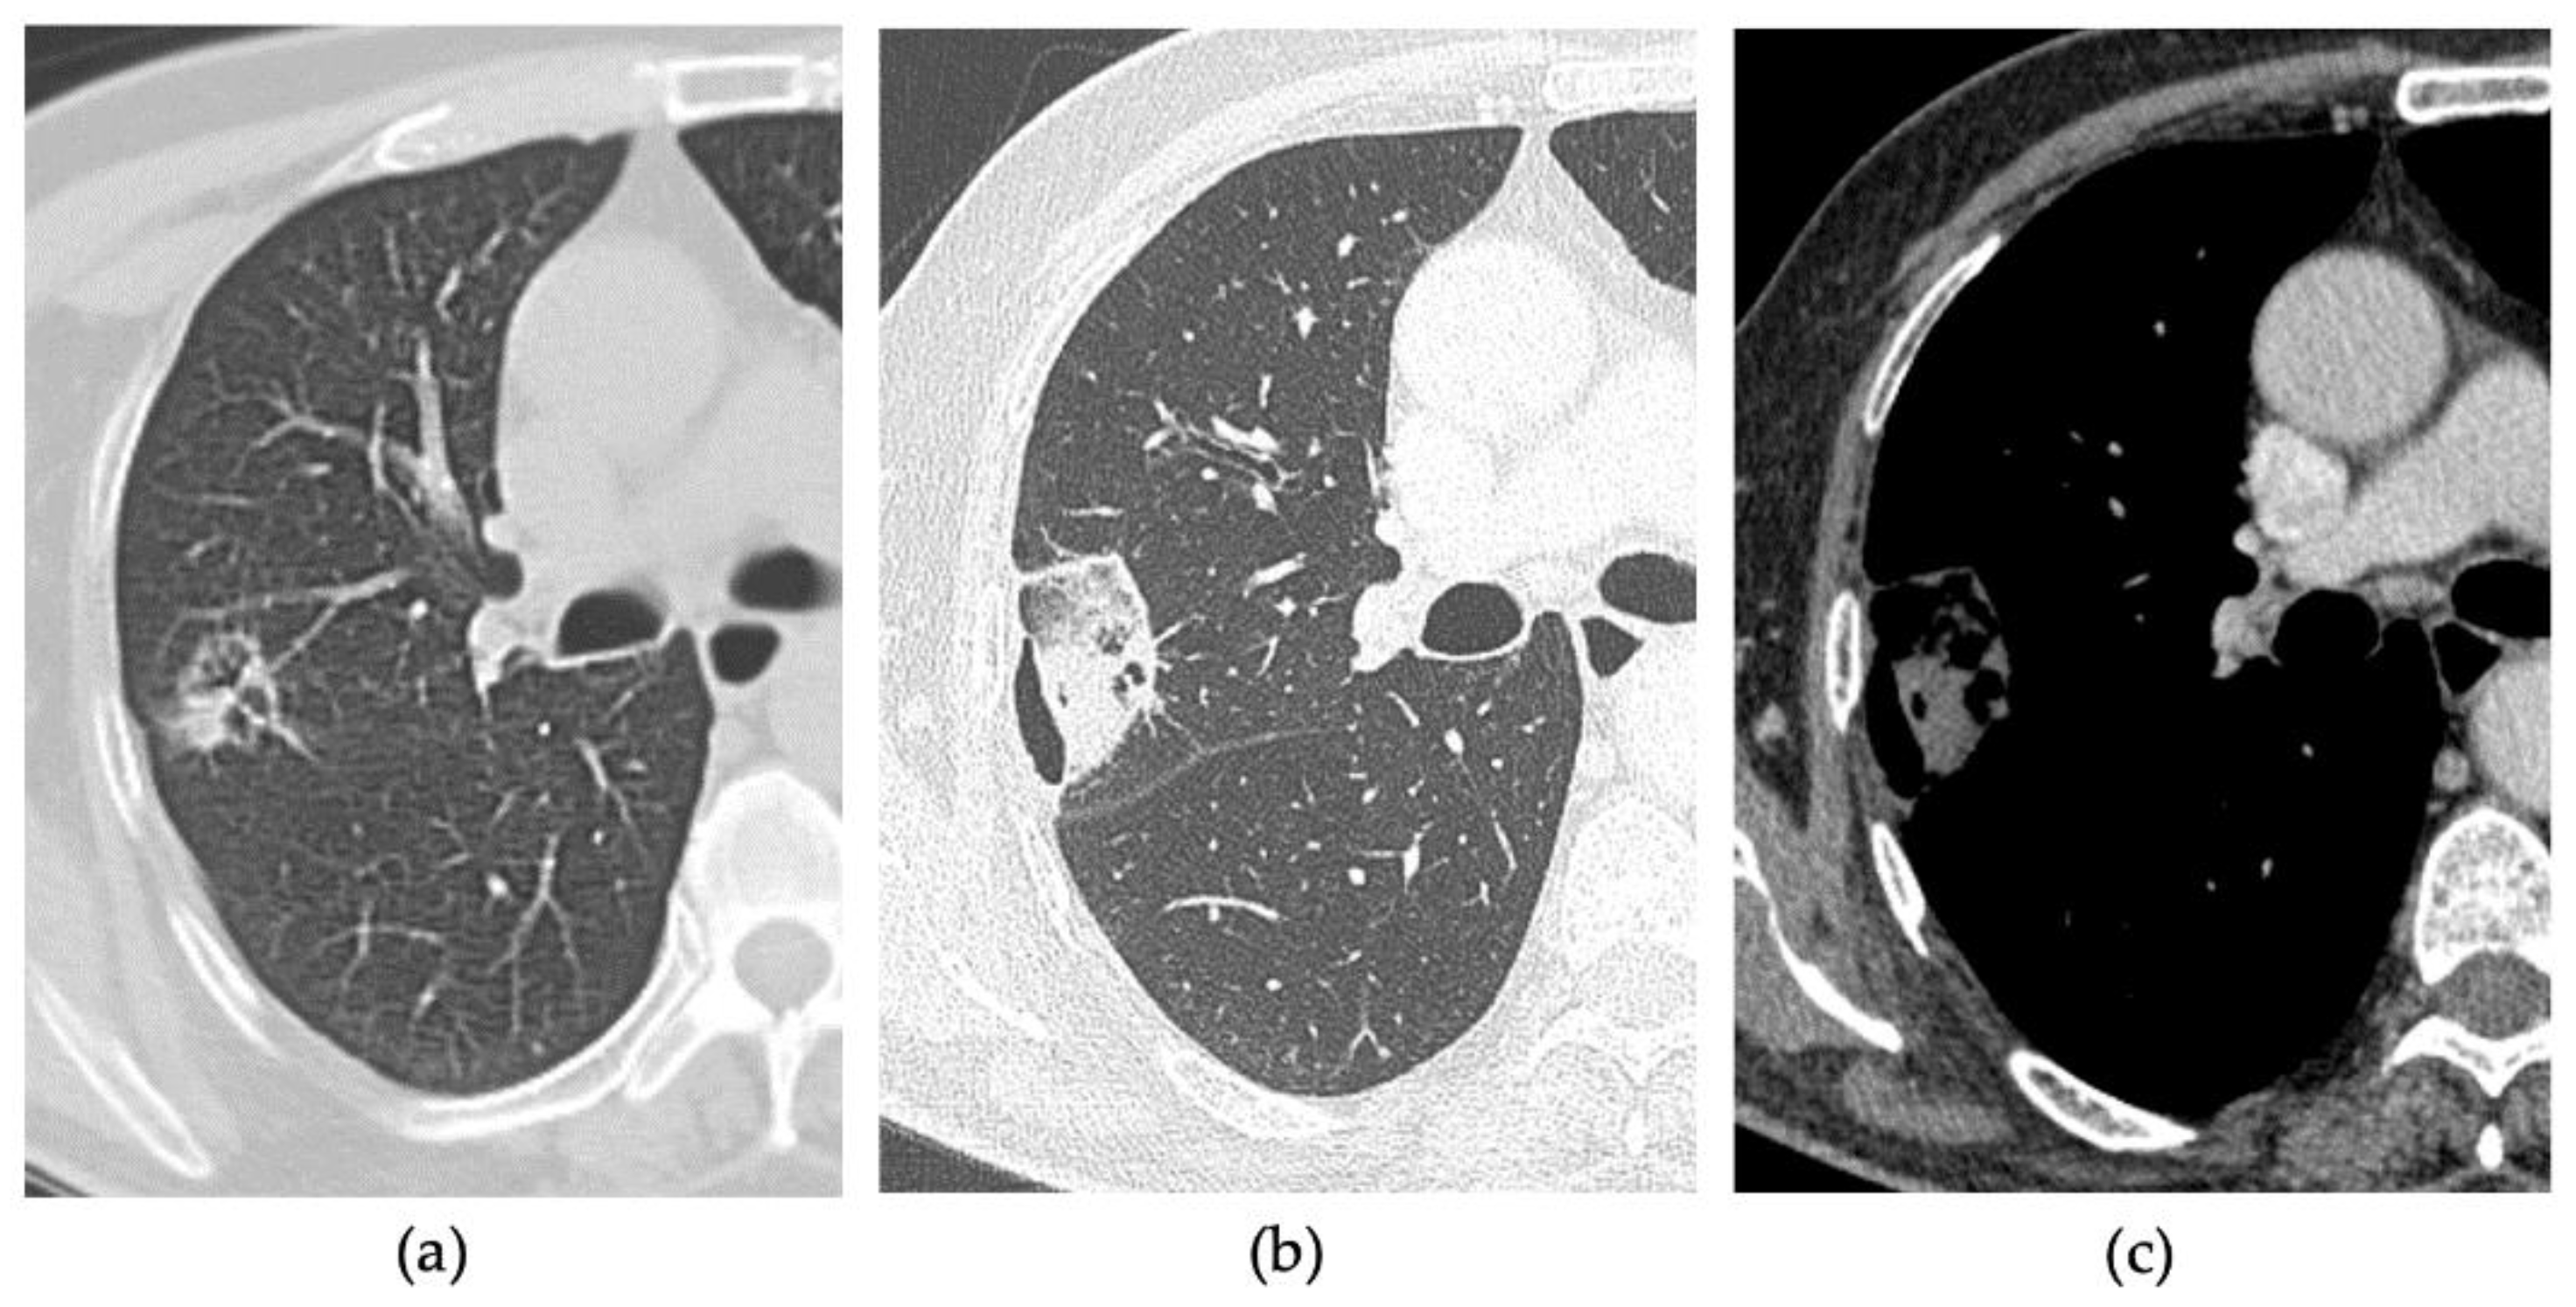

2.2. Procedure

2.3. CT Follow-Up